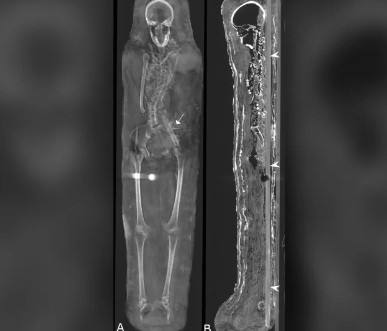

Các chuyên gia mới công bố thông tin đáng chú ý về 2 xác ướp được khai quật trong một ngôi mộ tại khu nghĩa địa cổ Saqqara, Ai Cập. Thay vì được đặt trong quan tài như nhiều trường hợp trước đó, hai xác ướp Ai Cập này được bảo quản theo cách đặc biệt.

Cụ thể, 2 xác ướp được quấn một lớp vải trước khi bao bọc bằng một lớp ván gỗ cực mỏng. Trên bề mặt của lớp ván gỗ là chân dung của người quá cố.

Kết quả kiểm tra cho thấy 2 xác ướp này qua đời vào khoảng năm 30 trước Công nguyên đến năm 395 sau Công nguyên.

Hai người này qua đời khi còn khá trẻ. Trong khi người đàn ông cao 1,64m qua đời khi khoảng 25 - 30 tuổi thì người phụ nữ có chiều cao 1,56m chết khi 30 - 40 tuổi.

Tuy nhiên, hiện các chuyên gia chưa thể tìm ra nguyên nhân tử vong của họ. Các chuyên gia mới phát hiện người phụ nữ gặp một số vấn đế về sức khỏe, trong đó có bệnh viêm khớp.